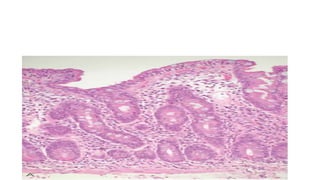

Biopsy

• INDICATIONS:-

• Documented or suspected steatorrhea or with chronic diarrhoea